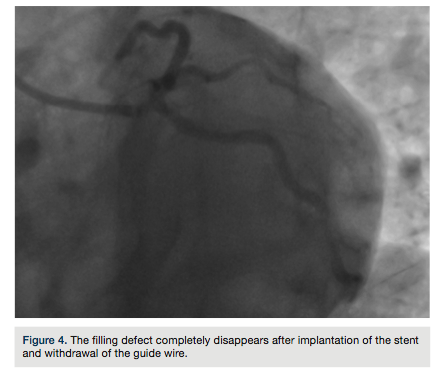

A Judkins left guiding catheter and soft guide wire were selected for the procedure. The stent (2.75 x 18 mm) could not turn into the Cx artery, due to the acute angle of the Cx origin from the left main coronary artery (LMCA) and inadequate support of the delivery system. An extra back-up (EBU) guiding catheter and an extra-support guide wire were utilized. A prominent filling

defect in the LMCA and proximal CX artery was encountered that was refractory to nitroglycerin and resembled coronary dissection, due to LMCA trauma from the EBU catheter (Figure 2). The patient had no clinical symptoms or EKG changes. A “pleating artifact” in the LMCA and Cx artery, induced by the stiff structure of the extra support guidewire, was felt to be likely due to the acute angle of the origin of CX artery from the LMCA. The guide wire was partially withdrawn and the filling defect decreased (Figure 3). A stent was appropriately placed into the in-stent restenosis without any complication. The filling defect completely disappeared after complete withdrawal of the guide wire (Figure 4).